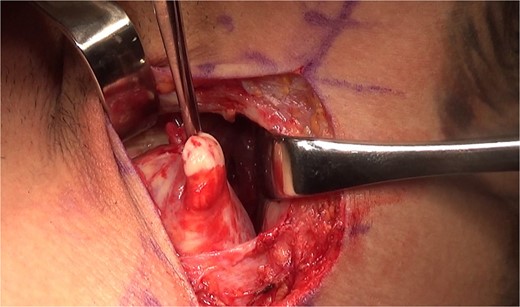

Given the complete rupture on the MRI and the high functional demand of the patient, surgical treatment was indicated and performed 10 days post-injury. The patient was positioned in a right lateral decubitus position with the left upper limb in 90° abduction (Fig. 3). A single 8 cm incision was made at the posterior axillary fold (Fig. 4). After identifying the radial nerve, a complete tear of the teres major at the myotendinous junction was visualized (Fig. 5). The tendon was tied with FiberWire (Arthrex, Naples, FL, USA) (Fig. 6) and its mobility confirmed. The humeral insertion site was exposed, debrided, drilled with two parallel holes 3 cm apart, and fixed with two Pec Buttons. The sutures were tensioned to stabilize the tendons. The shoulder’s range of motion was evaluated, confirming adequate repair tension (Fig. 7), and the incision was sutured. Final intra-op radiographic image is shown in Fig. 8. Post-surgery, no neurovascular changes were noted.